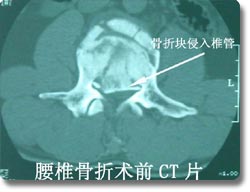

脊柱外科是该科的主要临床特色, 也是该科近年来发展的重点。在七十年代初就在国内率先开展了颈椎前路手术,大大拓展了新桥医院骨科脊柱手术治疗的范围,在全国享有较高的知名度。随后又积极开展了脊柱脊髓损伤的临床治疗和基础实验研究, 目前已治疗患者1000余例,其优良的治疗效果和精谌的手术技巧深得同行好评,使脊柱骨折复位成功率和截瘫的恢复率得到显著改善和提高。 |